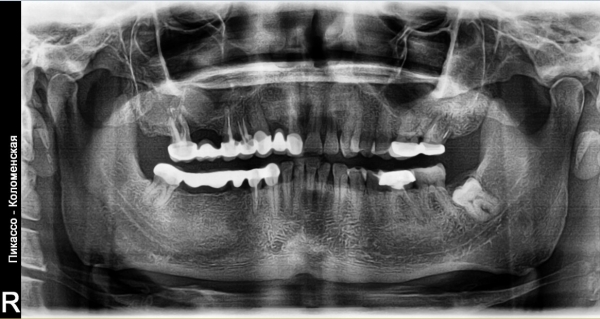

Добрый день. Мне в стоматологии сделали снимок зуба и сказали, что зуб надо удалять, так как вылечить не получится. Подскажите, так ли это? Может стоит обратиться к другим врачам? (фото зуба выслала на e-mail). Зуб № 46. На данный момент зуб не беспокоит. Три месяца назад был флюс, после разреза всё прошло. Антибиотиками не лечила, так как беременность. Сейчас срок 17 недель. Спасибо!

Да, к сожалению зуб необходимо удалить, так как на верхушках всех корней наблюдается обширное воспаление.